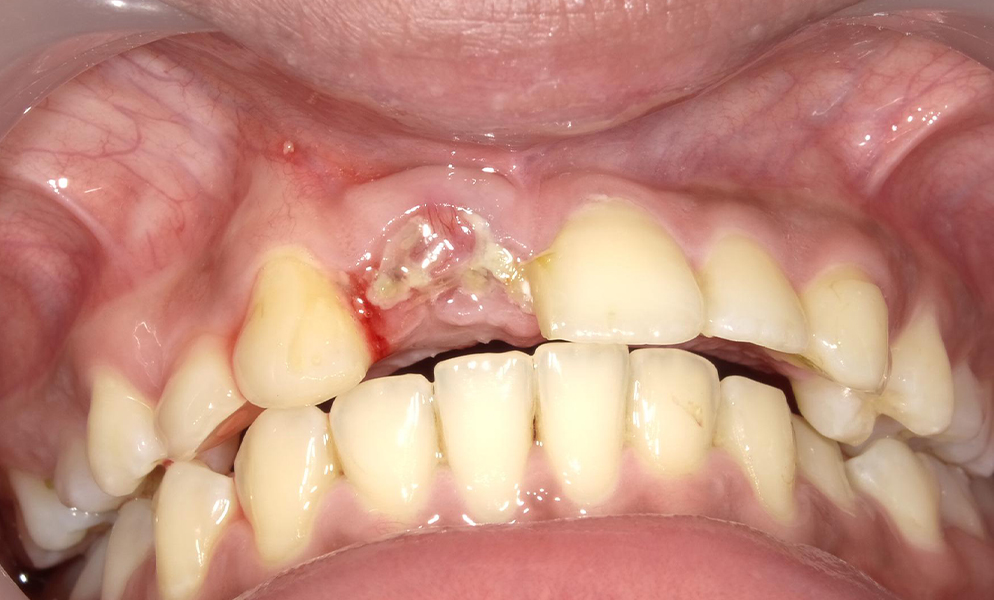

| Before | After |

![]() |

| Single anterior tooth missing space restored with a short dental implant (Bicon, USA) | |